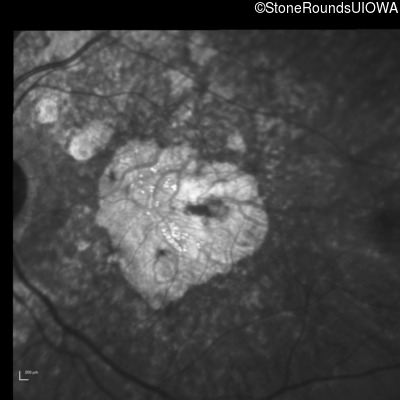

Blue Autofluorescence - Right - 20/20 -2

Exemplar